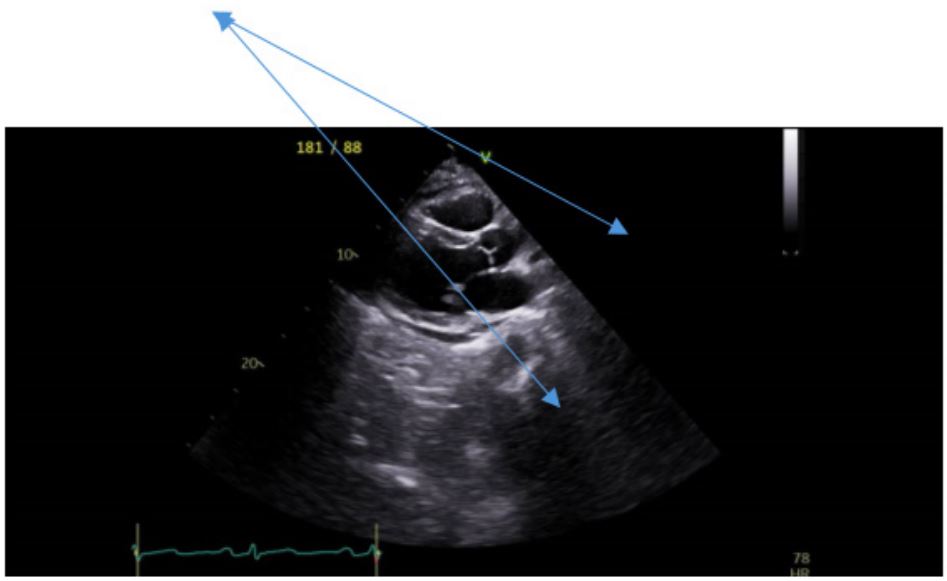

An ultrasound of the abdomen was performed in view of the elevation of the serum transaminases. The liver appeared normal but there was a suspicion of a pancreatic cyst. An abdominal CT scan did not show a pancreatic cyst but did detect a pericardial effusion. She therefore was referred for a transthoracic echocardiogram that revealed new-onset heart failure with hypokinesia in the inferior and septal walls and an ejection fraction of 45%, in addition to a moderate pericardial effusion. Coronary angiography revealed normal coronary arteries. The patient was discharged home on standard therapy consisting of bisoprolol, aspirin, atorvastatin and dapaglifozin.

Figure 2: Transthoracic echocardiogram revealing a pericardial effusion (arrow).

We present a case of a 56-year-old woman who was admitted for investigation of weakness and abdominal pain. She was usually healthy with no regular medication. Two weeks prior to her admission she developed severe vomiting and acute renal failure with a serum creatinine of 4.1 mg/dL. This resolved following supportive treatment with iv fluids. A review of her laboratory tests showed an elevation in her serum transaminases together with an increase in CKMB and a subsequent increase in LDH (Table 1). Abdominal imaging by ultrasound and CT scan was normal but did detect a pericardial effusion 1. At this stage transthoracic echocardiogram was carried out (Figure 2), which detected inferior and apical hypokinesia together with an ejection fraction that was reduced to 45% and a pericardial effusion. Coronary angiography revealed normal coronary arteries.